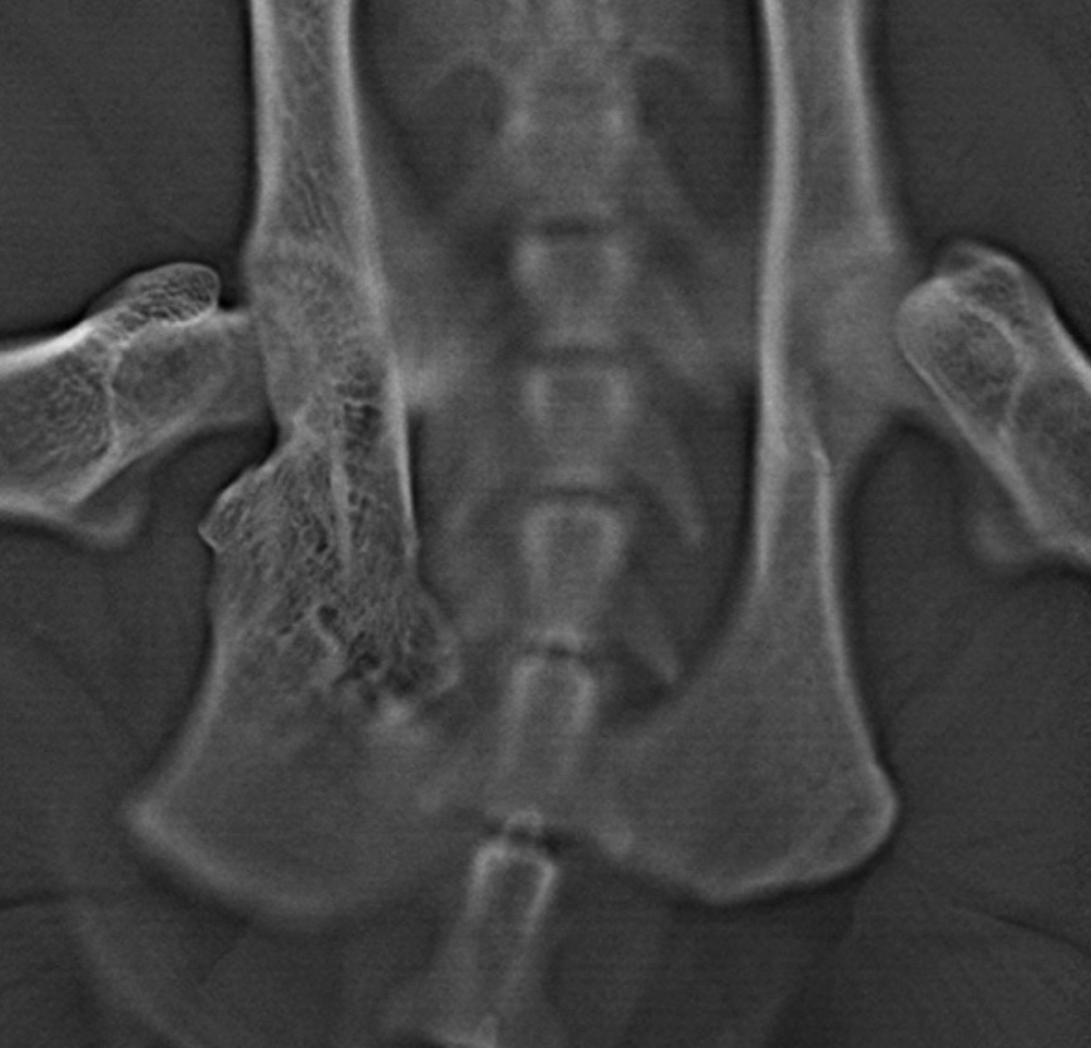

DT was used to identify the site of most significant pelvic canal diameter loss to determine the optimal approach for surgical widening of the pelvis. In addition to confirming pelvic fracture malunions (Figure 3), the DT image stacks demonstrated the exact site of severe narrowing of the colon and rectum at the level of the narrowing in the pelvis (Figure 4).

Somewhat surprisingly, the majority of pelvic canal stenosis, as identified by colon and rectum narrowing, did not appear to be associated with bone deformities.

Stenosis was largely associated with non-mineralised material within the pelvic canal. A generous mass of fibrocartilaginous callus within the pelvis was suspected. Additionally, surgical planning was aided by the appearance of a right obturator foramen, which was almost entirely occluded by the presence of the cranial aspect of the right ischium (Figure 5).

The obturator foramen is an important landmark in TPO, since two of the osteotomies (that of the pubis and the ischium) extend into this foramen. The narrowing of the pelvic canal and the level at which this was most severe was more clearly appreciable from the DT stack.